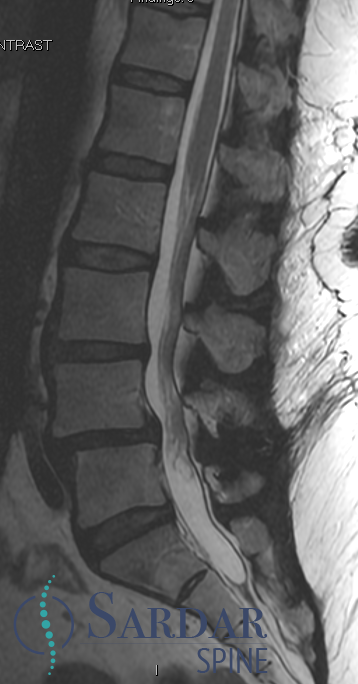

From robotics and AI-driven surgical planning to virtual modeling and custom implants, I’ve embraced a combination of tools that allow me to create tailored surgical plans for my patients—particularly those with scoliosis and spinal deformities.

What sets my approach apart is the seamless integration of these advanced technologies to ensure unparalleled accuracy and better outcomes for each patient.